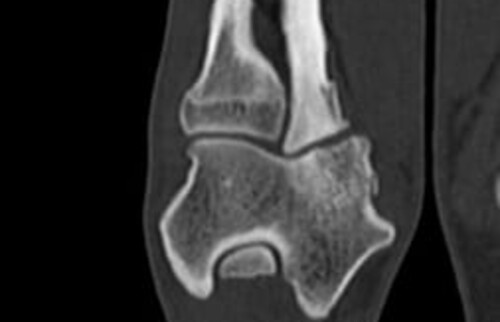

Nach der klinischen Diagnose werden die Hunde in unserer Klinik direkt im Computertomografen untersucht, sodass genau beurteilt werden kann, welche Gelenksanteile wie schwer betroffen sind, um eine individuelle Therapie festzulegen.

Schwarz-weiss Röntgenaufnahme